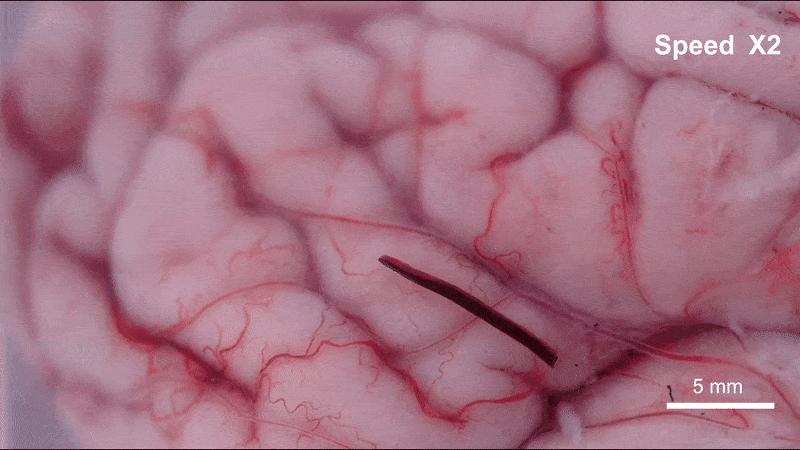

離體豬腦皮層上運動的“線蟲”機器人

(圖片來源:研究團隊供圖)

具體來說,在外部可編程磁場的作用下,這根毫米級的纖維機器人可以以三種仿生模式靈活轉換:在交變磁場下,它會像線蟲一樣產生縱向的波浪形擺動,形成持續的推進力;當需要依附組織表面時,纖維表面的微弱粘附力讓其能抓住微小固定點,並通過自身的波浪形變完成蠕動前行;而在面對通道急轉或截面突變的拐點時,機器人會切換到滾動模式,帶着磁性顆粒沿着自身軸線翻滾,輕鬆越過障礙。這些精妙的運動機制經過3D打印的大腦溝回仿真模型和離體豬腦實驗雙重驗證——血凝膠纖維機器人能夠連續通過數級米字型擋塊,抵達預設的目標位置,並且全程未對軟組織造成任何機械損傷。